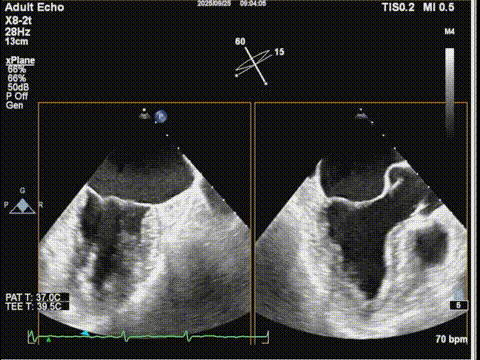

术前食道超声:

房颤,瓣环扩大的房性二尖瓣反流,反流主要集中在二区,二区后叶部分脱垂,后叶的长度16mm,前叶的长度是37mm。房间隔整体的条件可,从瓣环到拟定的卵圆窝顶部高度大概是41mm。

二尖瓣2区

二尖瓣2区color